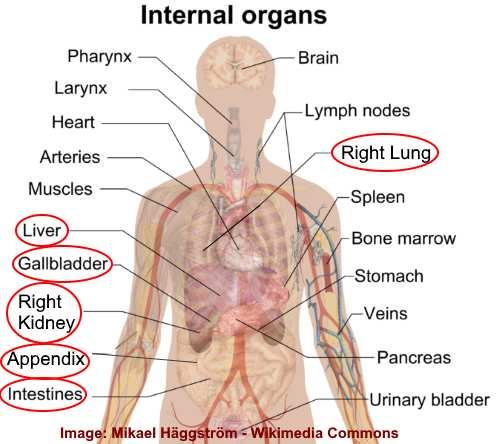

Anatomy Of Internal Organs Female – Organ Anatomy Female Anatomy …

Right Side Women’s Body Human Body Organs / Human Anatomy And …

Female Body Organs Diagram Anatomy | MedicineBTG.com

Human Anatomy Picture Organs Female Human Body Diagram Of Organs See …

Right Side Women’s Body Human Body Organs : What Do Right-Sided Organs …

Female Human Organs Diagram | MedicineBTG.com